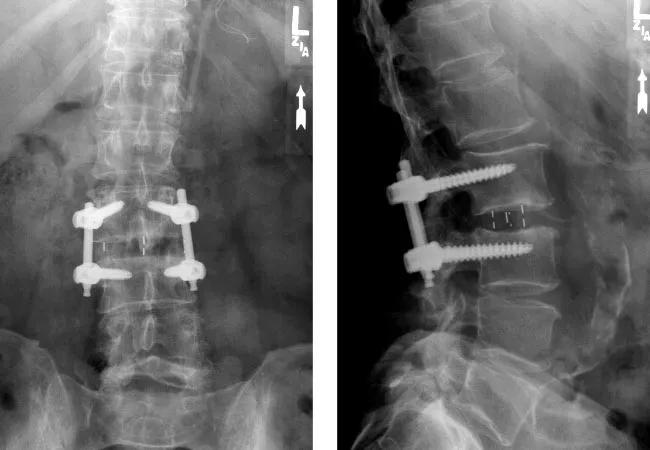

x-rays of hardware between spine segments

Two recent systematic reviews and meta-analyses underscore a key message for spine specialists: diabetes and obesity significantly compromise outcomes following spinal fusion surgery. The analyses, which collectively evaluated data from 180,000 patients, revealed increased risks of nonunion and worse patient-reported outcomes in individuals with these conditions who underwent spinal fusion.